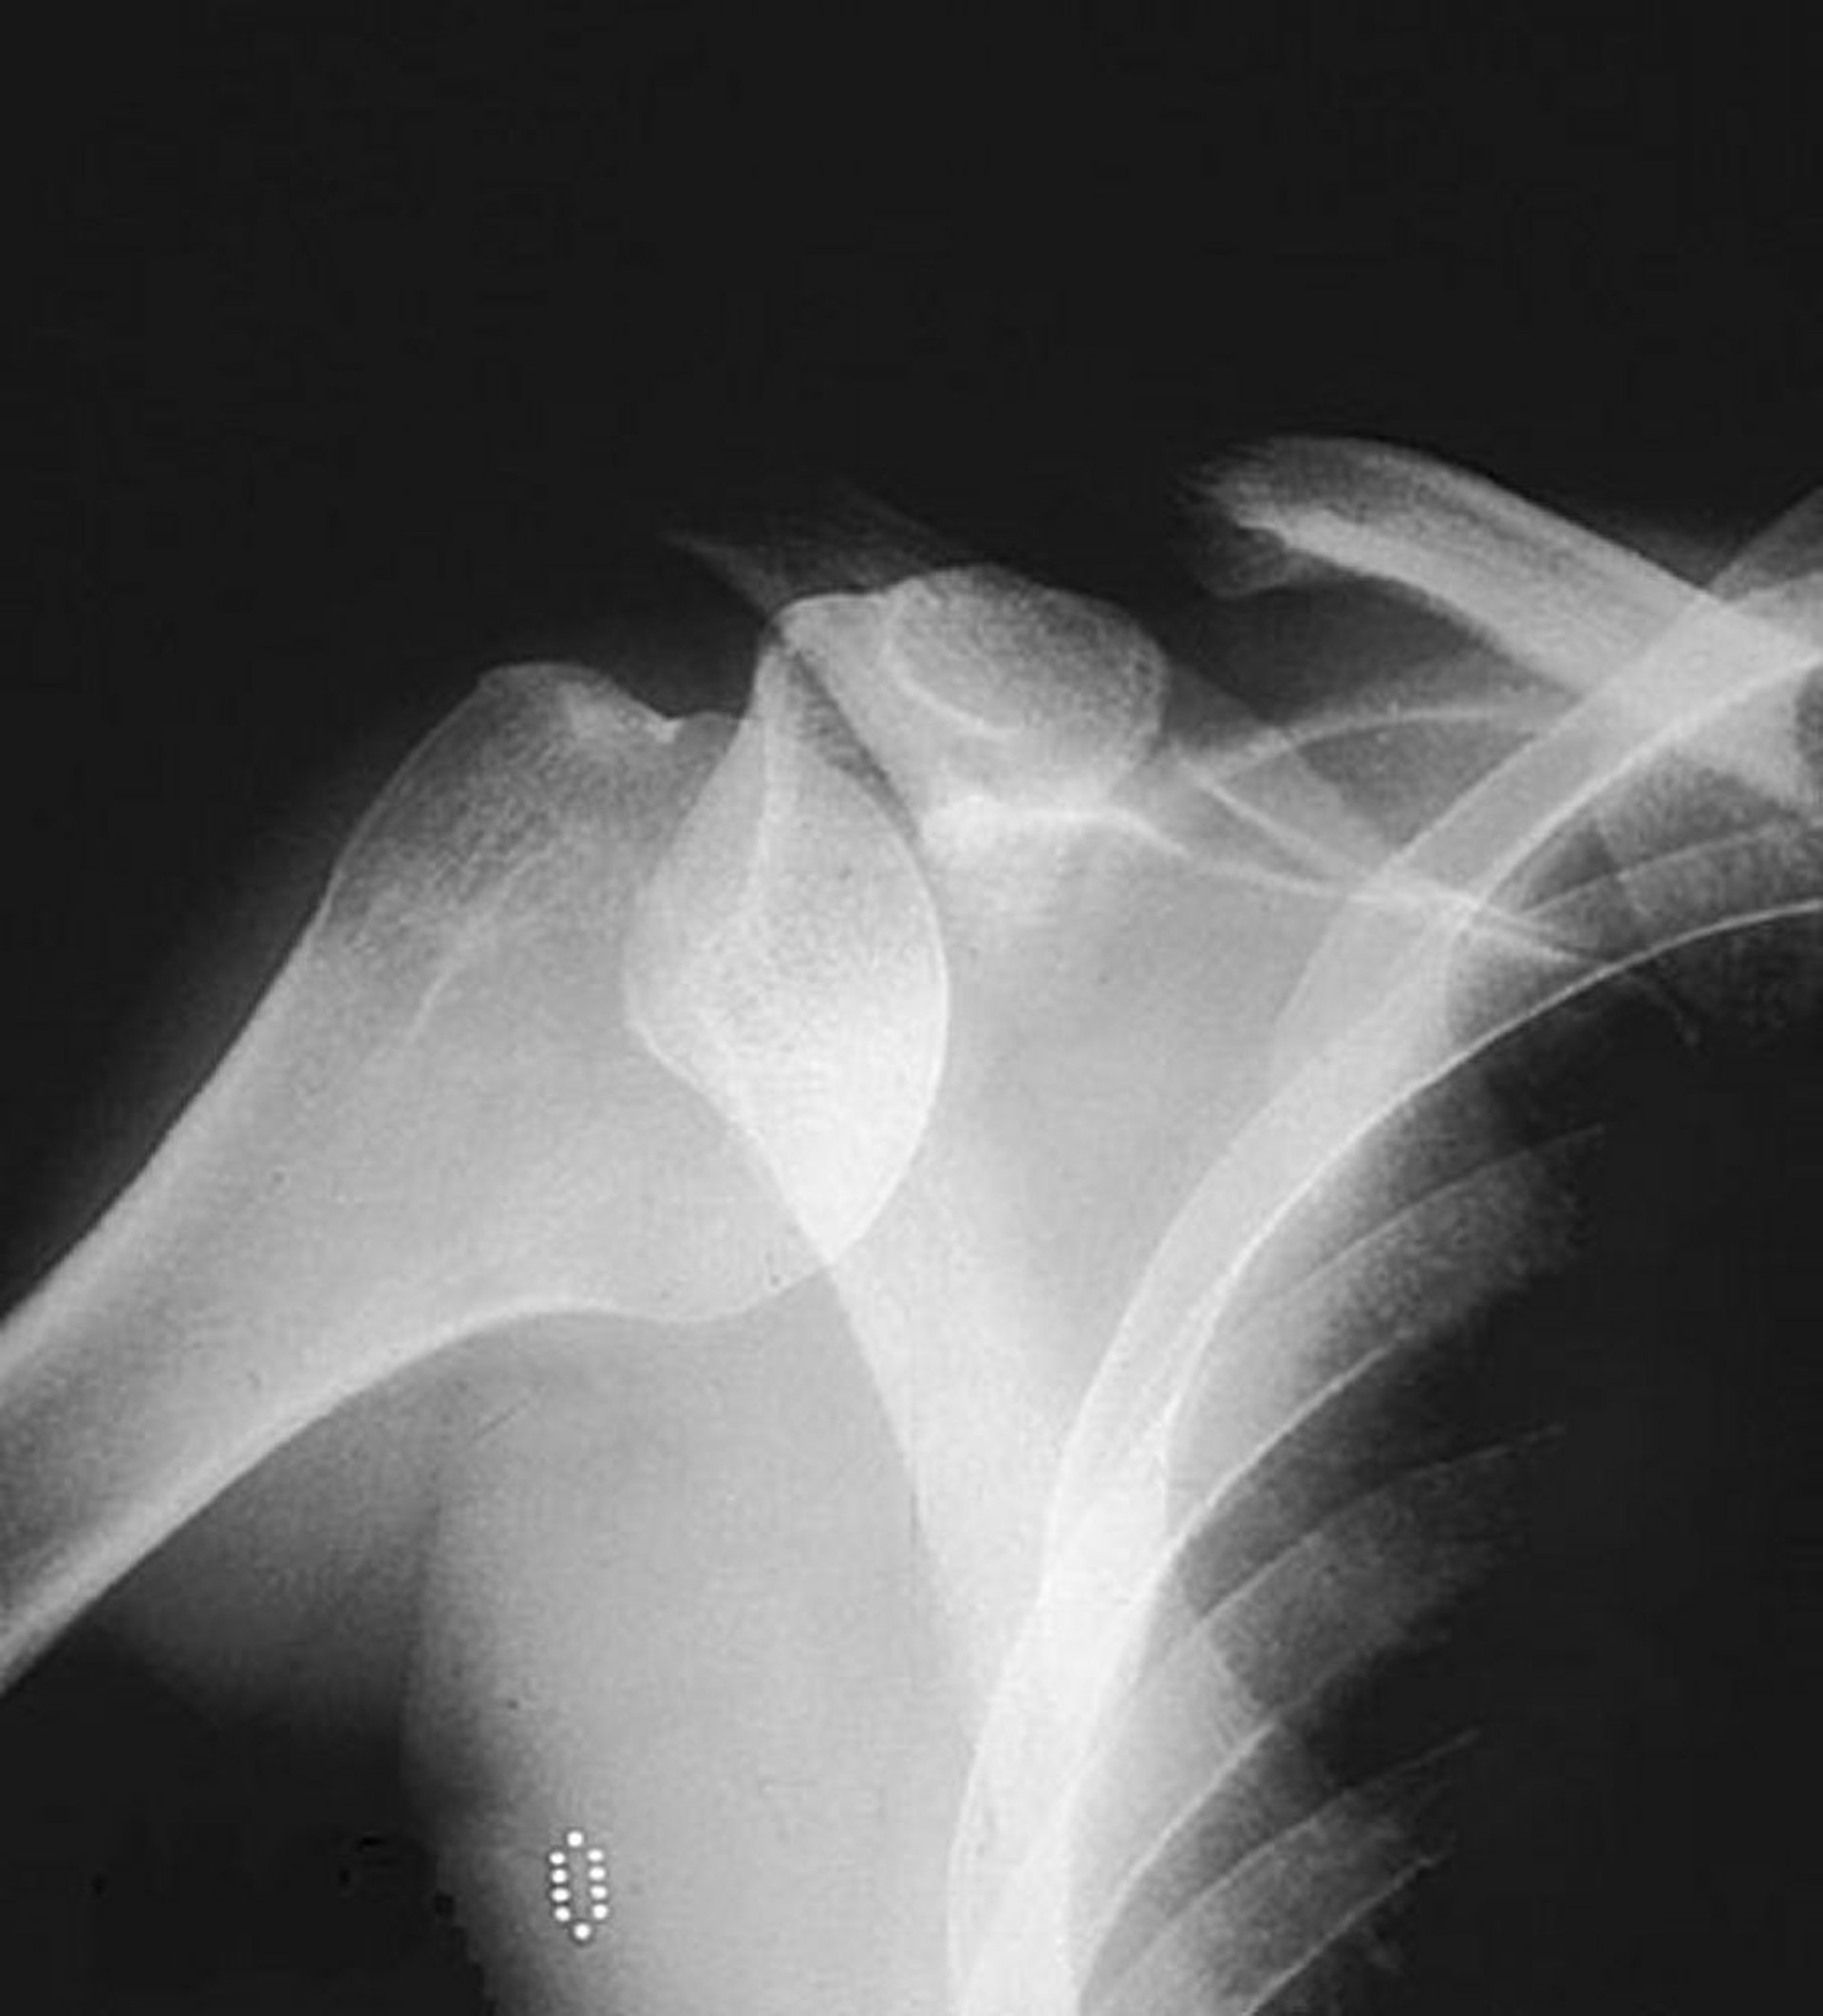

Trật khớp ổ chảo cánh tay (vai) trước

Chụp X-quang không chuẩn bị phim thẳng cho thấy chóm xương cánh tay ra khỏi vị trí thông thường của nó trong ổ chảo, gợi ý trật khớp trước.